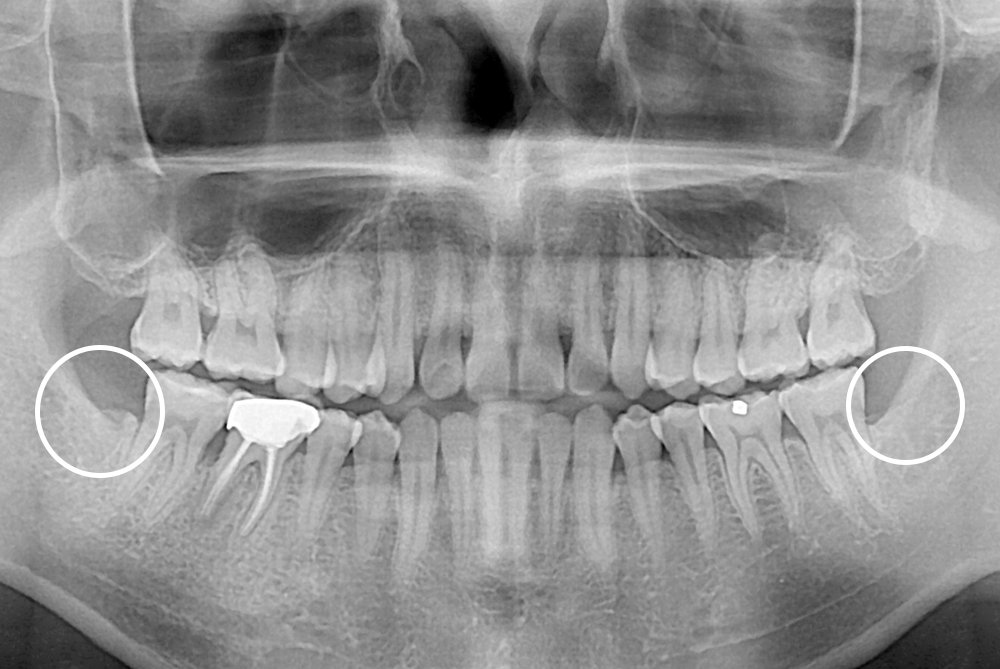

치료후 : 2017-07-26

세종치과는 구강악안면외과학 박사이신 원장님이 발치하는 치과 입니다.